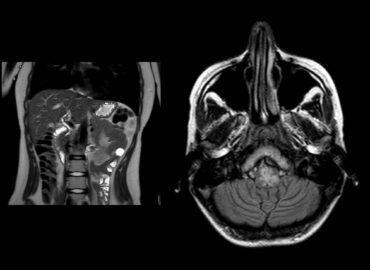

Paciente masculino de 56 años con APP de DM2, que es derivado a nuestro servicio con diagnóstico de síndrome […]